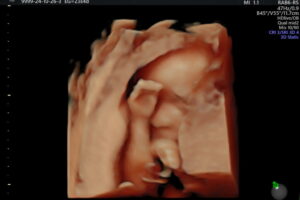

Galería de recuerdos felices Las primeras fotos de Ambar y la historia de sus papás-